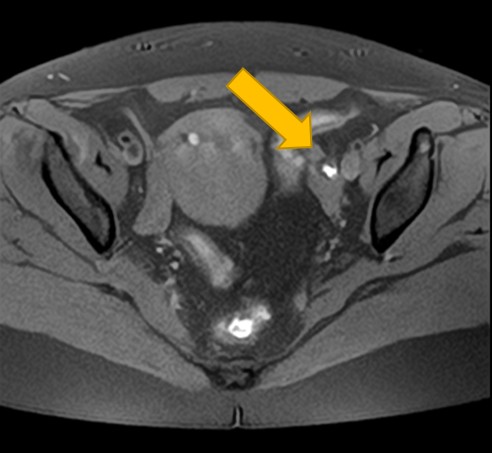

2. 卵巣腫瘍(嚢腫)のMRI:良性・悪性を判断する「中身」と「充実部分」の評価

卵巣嚢腫の中身が液体、脂肪、血液など何であるか、嚢腫壁の性状(肥厚、隔壁の有無)、充実部分の有無や血流を評価することで、良性か悪性(がん)かの可能性を判断する重要な手がかりとなります。

必要に応じて造影剤を使用することで、病変の血流状態も評価でき、良性・悪性の判断に役立ちます。

| 卵巣嚢腫 | 嚢腫の中身(液体・脂肪・血液など)、壁の厚さ、隔壁や充実部分の有無、内部の血流評価による良悪性の可能性。 |